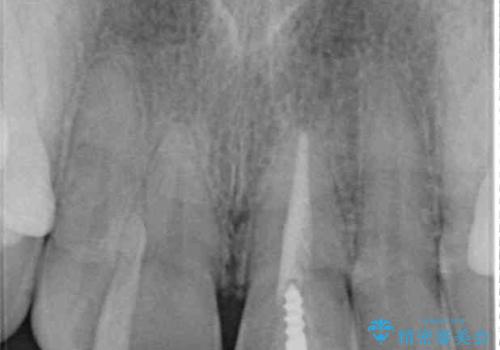

- 前歯のクロスバイトと神経を取り除いた後に変色してしまった前歯を気にして来院された患者様です。

ワイヤー矯正により矯正治療を行った後に、前歯の補綴治療を行うこととしました。

変色してしまった前歯は、反対側の歯と比べて歯肉が覆い被さっていたため、骨整形を含めた歯周外科処置を行い、歯肉ラインを整えることとしました。